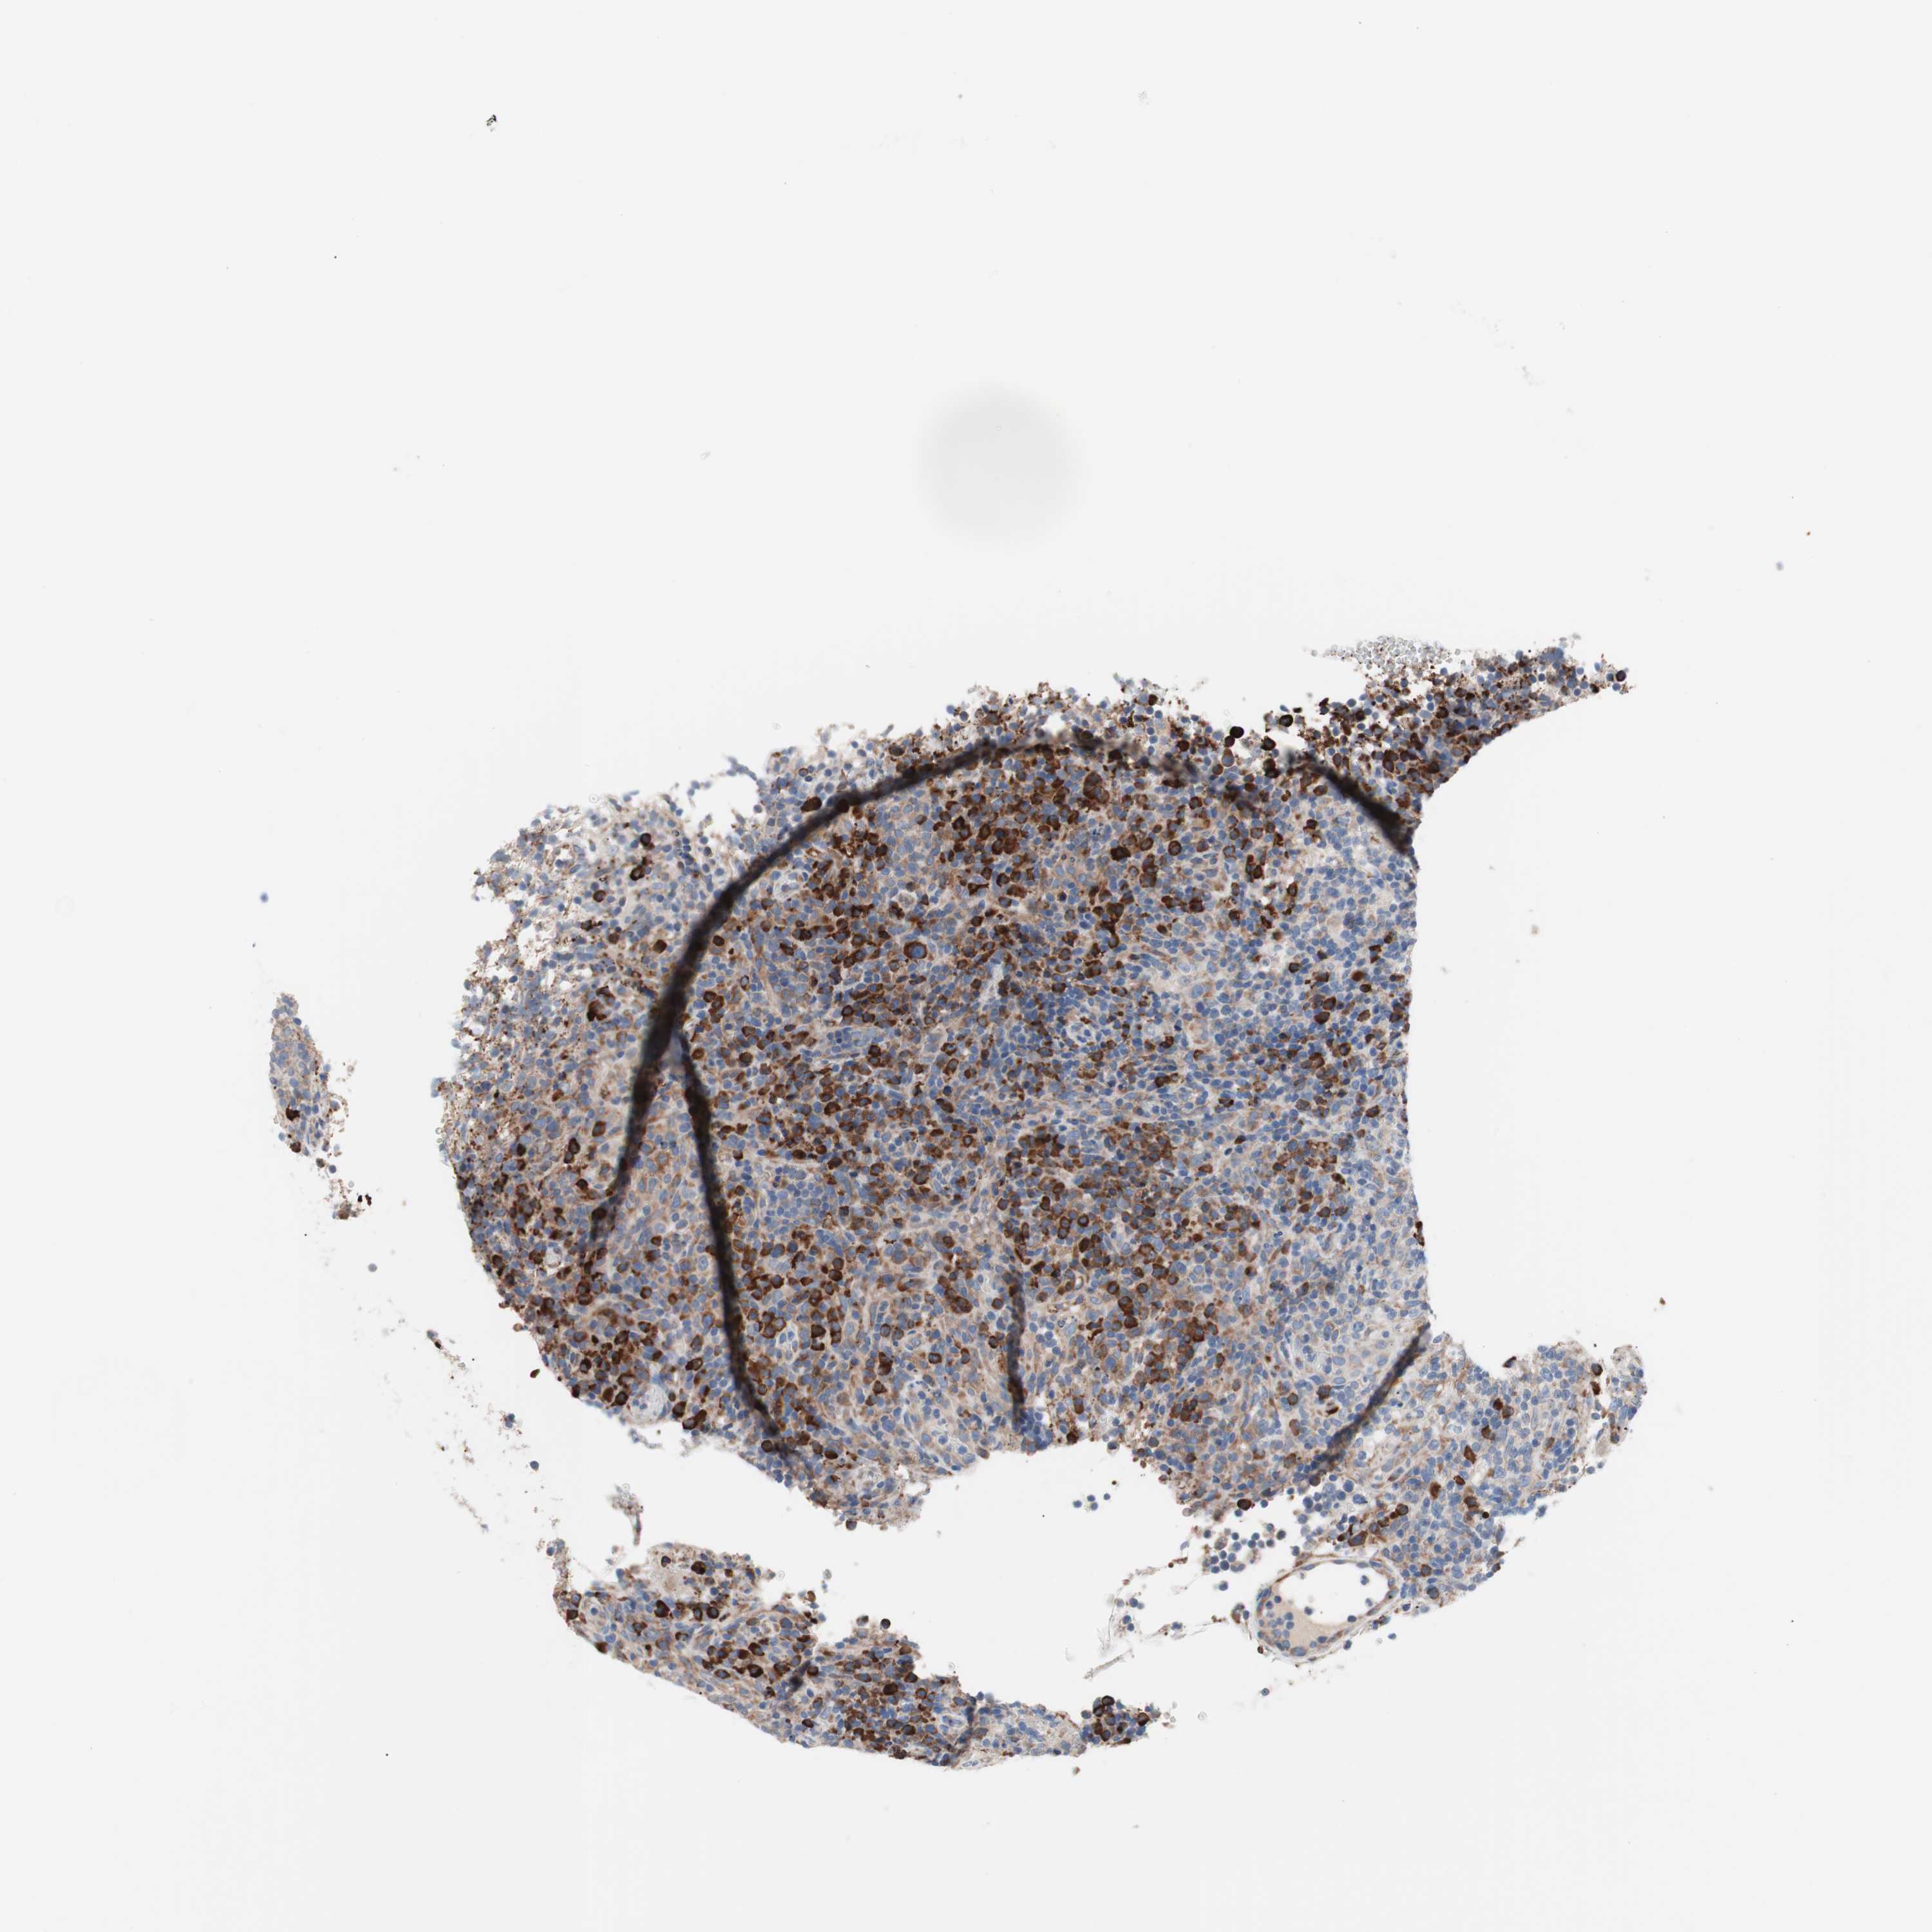

LYMPHOMA - Protein expressioni

A mouse-over function shows sample information and annotation data. Click on an image to view it in a full screen mode. Samples can be filtered based on level of antibody staining by selecting one or several of the following categories: high, medium, low and not detected. The assay and annotation is described here.

Antibody stainingi

Antibody staining in the annotated cell types in the current human tissue is reported as not detected, low, medium, or high, based on conventional immunohistochemistry profiling in selected tissues. This score is based on the combination of the staining intensity and fraction of stained cells.

Each image is clickable and will lead to virtual microscopy that enables deeper exploration of all samples and also displays staining intensity scores, fraction scores and subcellular localization as well as patient and tissue information for each sample.

Antibody HPA007293

Staining

High

Medium

Low

Not detected

Intensity

Strong

Moderate

Weak

Negative

Quantity

>75%

75%-25%

<25%

None

Location

Nuclear

Cytoplasmic/membranous

Cytoplasmic/membranous,nuclear

Hodgkin's disease, NOS

Malignant lymphoma, non-Hodgkin's type, Low grade

Malignant lymphoma, non-Hodgkin's type, High grade